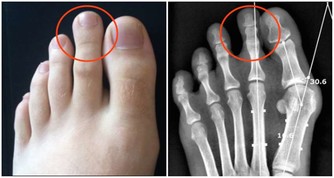

3、注意腿部保暖以及排汗

身體濕氣過重,有很大的一部分原因是由於我們不注重身體的保暖導致的。在夏天我們身體的濕氣會更加多。特別是在回南天的時候,感覺身體濕漉漉的,渾身不自在。而在這時候,要注意對腿部進行保暖,不要讓腿過度暴露在空調底下。也要注意排汗,濕氣是可以隨汗液而排出的。